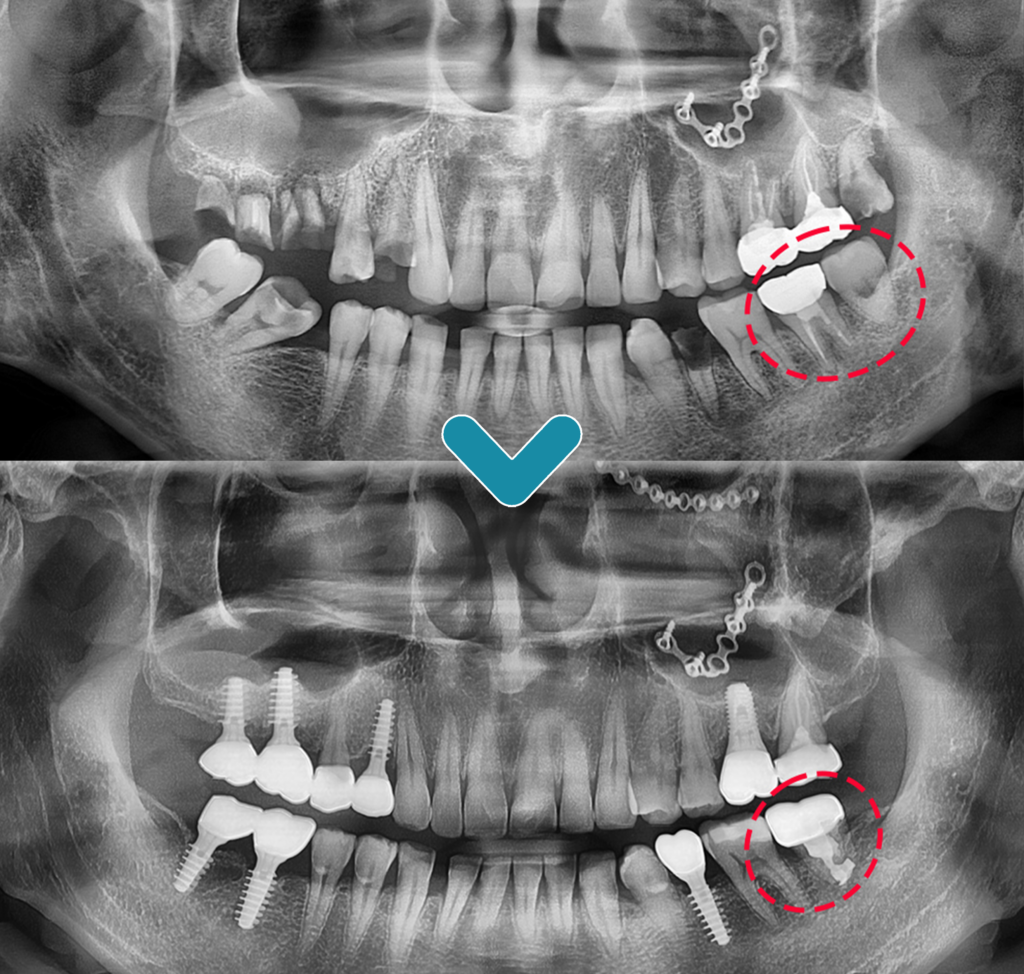

오늘은 사랑니를 어금니로 이식하는

치아이식술을 진행하신 환.자분을

소개해 드리려고 합니다.

왼쪽 아래 어금니 부위의 경우에는 다행히

사랑니가 문제없이 건강하게 존재하고 있었으므로

예후가 좋지 않은 어금니를 발치한 후

사랑니를 그 자리에 이식하는

치아이식술을 진행해 보기로 결정하였습니다.

사랑니를 어금니 부위에

이식하여 크라운 치료를 한 뒤

5년이 지나고 난 후에도

문제없이 사용하고 계셨는데요.